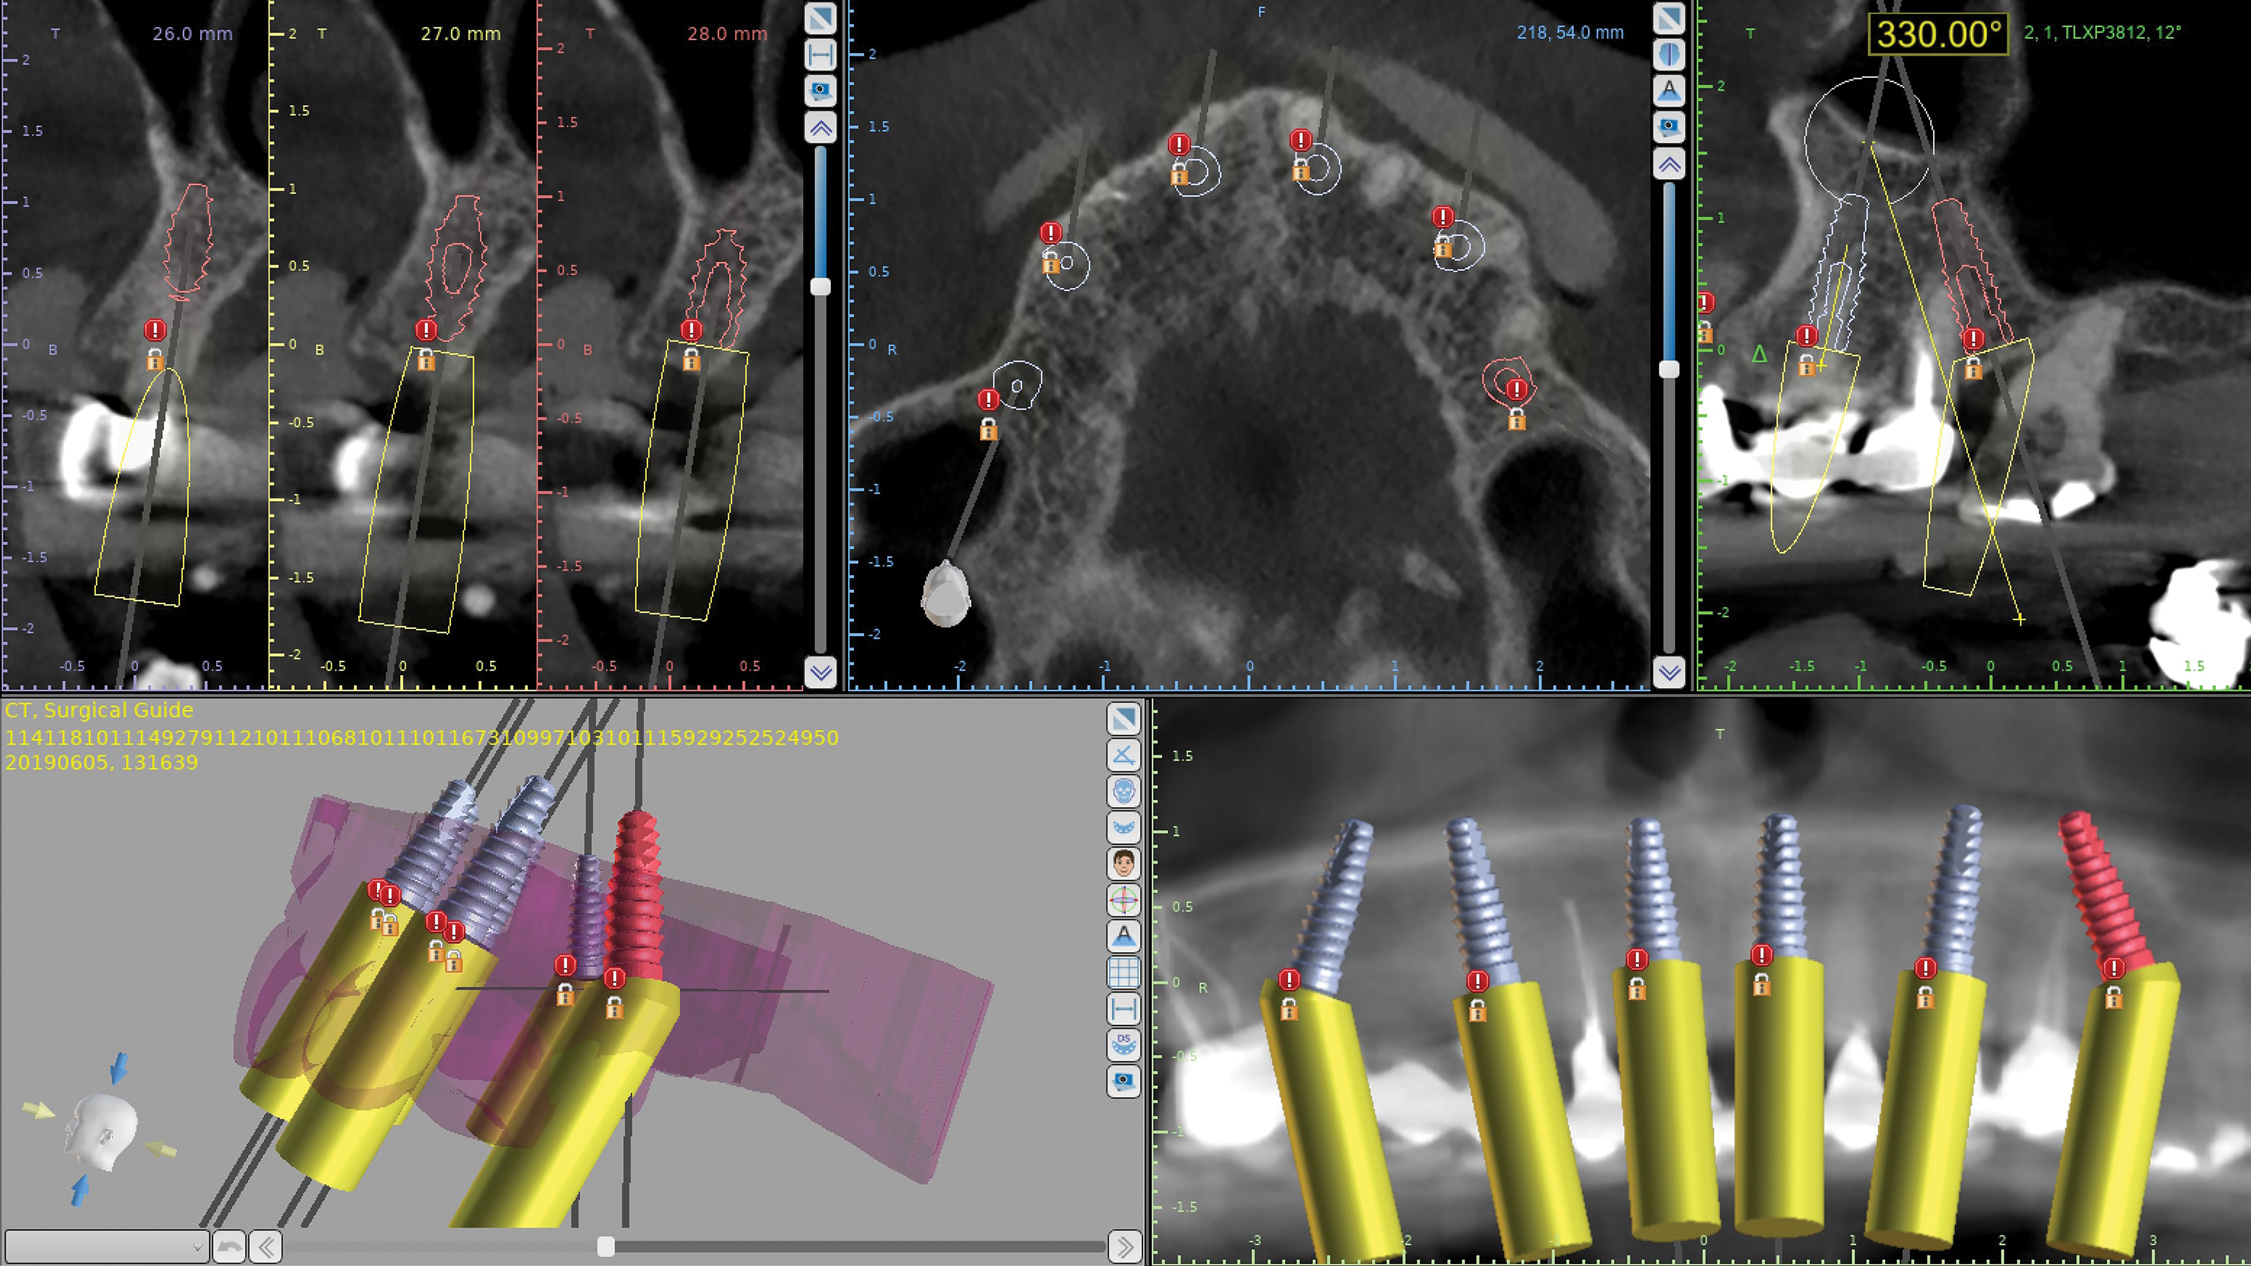

Implant positions are planned based on the desired final prosthetic positions of the teeth (whether natural teeth, denture teeth, or a digital wax-up, which are visible in the software) (Figure 4) and available bone. In this case six tapered implants were planned, with the four anterior implants planned parallel to each other and the two distal-most implants planned at 30-degree angles to the four anterior ones. The plan included the use of 30-degree angled multiunit abutments to correct the distal implant angulations. Placing six implants across the arch reduces stress on the implants through enhanced distribution and reduced cantilevers.21,22 By planning the use of angled multiunit abutments and placing the implants using a surgical guide the restorative procedures can be simplified and the try-in or replacement of the multiunit abutments avoided.23

Fig 4. Virtual plan based on desired prosthetics.

Figure 4

Fig 7. Virtual design of stacked drilling guide.

Figure 7